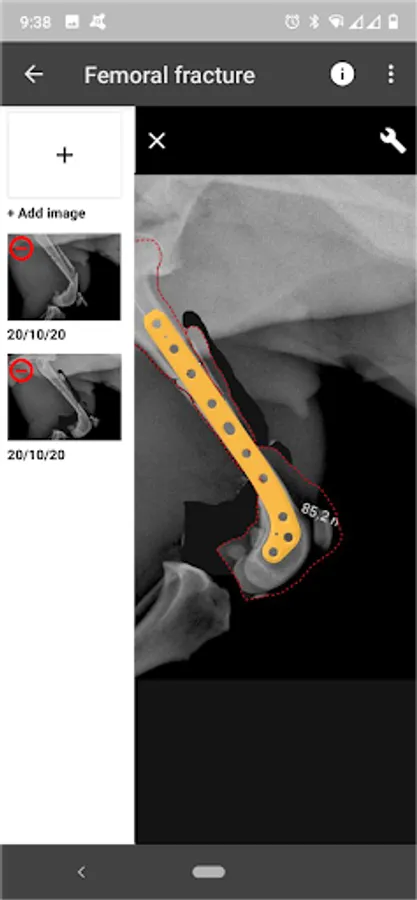

BETA Implants is leading with its vision of personalized surgery and has a wide catalogue the specific locking implants for trauma and orthopedic surgery for veterinary.

Following our service of direct technical assistance between our biomedical engineers and the surgeon, the BETA app is the digital planning solution development for planning your trauma and orthopaedic procedures with BETA implants: BETA app.

BETA App is a Virtual Surgical Planning tool that provides surgeons a solution designed to make surgery more predictable and efficient.

4. Catalogue of BETA Implants locking plates, in 2.0, 2.4, 2.7 and 3.5 sizes:

d) Diaphyseal femur plates

5. Share your results

6. Save in project